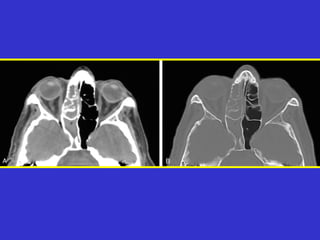

Este documento describe las diferentes proyecciones radiográficas utilizadas para examinar los senos paranasales, incluyendo las proyecciones básicas de Caldwell, Waters lateral y las proyecciones especiales como Hirtz y Waters mentonasal. También describe las diferentes estructuras anatómicas que componen el complejo ostiomeatal anterior y posterior de los senos paranasales.